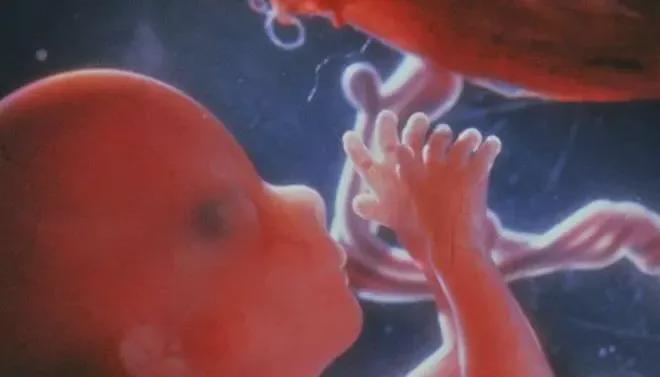

从成分上看,羊水98%以上是水,同时还含有少量电解质、蛋白质、激素,以及胎儿脱落的细胞等,对胎儿来说,是一个非常重要的生存环境。

水分和营养物质通过胎膜渗透进入羊膜腔,为胚胎提供最基础的生长条件。 这一阶段,羊水更像是“妈妈身体的一部分”。

当孕妇走路、转身、轻微碰撞时,外界的冲击力会被羊水大幅削弱,避免直接作用在胎儿身上。 同时,羊水还能防止胎儿与子宫壁直接摩擦,减少压迫风险。

胎儿在子宫里虽然不能真正呼吸,但会通过吞咽羊水、做“呼吸样动作”,刺激肺部发育。

这些看似简单的动作,其实是在为出生后的自主呼吸做准备。 同时,吞咽—排泄的循环,也在悄悄锻炼胎儿的消化系统。

不管外界气温如何变化,胎儿都能在羊水中保持相对舒适的状态,这对器官发育非常重要。

从胚胎初成到顺利分娩,羊水一直在默默守护着胎儿,也在支撑着母体完成这场生命的合作。